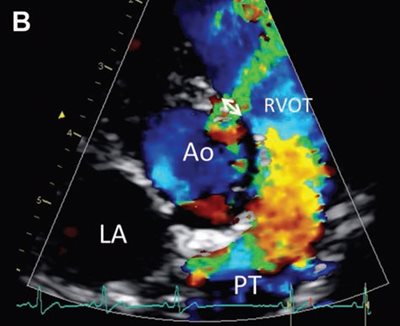

Figure 1—Representative color flow Doppler mode echocardiograms used to visualize the VSD and measure the maximal VSD size (ie, VSD diameter) in a cat (A) and a dog (B).

B—Visualization of a left-to-right shunt through a small supracristal VSD and measurement of the maximal diameter of the defect (double-headed arrow) on the right parasternal shortaxis view at the level of the aortic valve. Scales on the left side of each image represent distance to the transducer (in cm).

Ao = Aorta. LA = Left atrium. LV = Left ventricle. PT = Pulmonary trunk. RV = Right ventricle. RVOT = Right ventricular outflow tract.